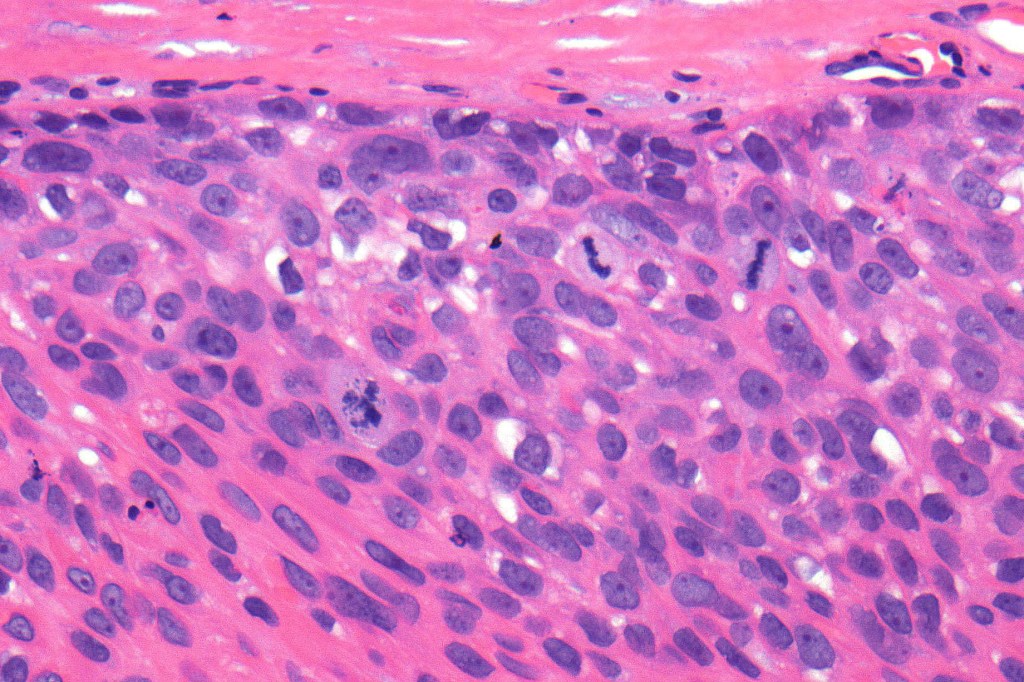

•Nuclear pleomorphism and nuclear hyperchromatism

•Marked mitotic activity

•Abnormal mitoses